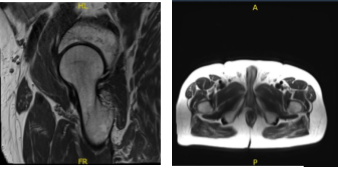

He visited after a week for a follow up and presented the results of his MRI and showed mild left hip degenerative change with insertional gluteus Medius tendinosis and partial tearing with mild greater bursitis. Mild RIGHT hip degenerative change. Insertional gluteus minimus tendinosis and partial tearing with mild greater trochanteric bursitis.

MRI-3T left hip non-contrast